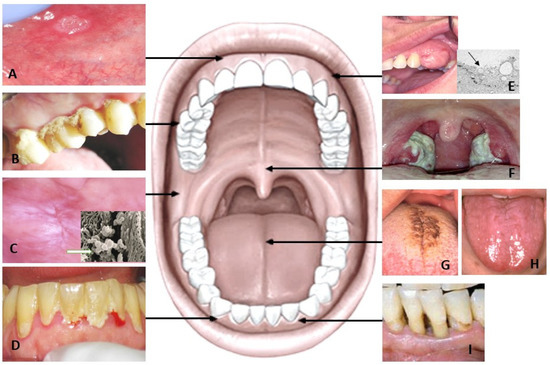

2. Sources of Salivary Metabolites in Healthy Subjects

Saliva is an oral fluid secreted by the major and minor salivary glands. After entering the oral cavity, it is referred to as mixed or whole saliva, supplemented with many constituents originating from blood, mucosal cells, immune cells, and microorganisms [9]. Whole saliva represents the complex mixture of a variety of molecules and hence, it is valuable to use in research. The composition of saliva and oral microbiota differ in healthy subjects most likely due to age, gender, habits, diet, oral hygiene, medication, and different oral niches (prothesis, tooth fillings, tongue disorders, sebaceous glands = Fordyce granules) (Figure 1).

Figure 1. Summary of oral metabolite sources that may take part in salivary metabolic fingerprint in healthy subjects. Saliva is secreted by salivary glands in salivon with acinar and ductal cells. Metabolites are obtained also from oral mucosal cells (AD) and gingival crevicular fluid (F). Most of salivary metabolites are produced by oral micro-organisms (E). Sebaceous glands referred as Fordyce granules (arrow) are located in the buccal mucosa (G). Dentition and dentures (H) form different niches for attaching of micro-organisms. Oral hygiene, diet, and habits, including smoking and alcohol consumption, differ salivary metabolite profile (I).

The oral microbiome is a set of diverse micro-organisms that inhabit different niches of the oral cavity. They, together with salivary defence, play a key role in the oral balance between health and diseases. Oral microbes communicate with oral epithelial cells via Toll-like receptors (TLRs) which plays a key role in the oral immune system producing inflammatory cytokines. Studies using scanning electron microscopy (SEM; Figure 1B) showed no or very few micro-organisms on the buccal mucosal surface. Instead, most of the mucosal microorganisms are located on the dorsal tongue surface (Figure 1C), especially on the surface of rough hyphae of filiform papillae (Figure 1D).

Fordyce granules (FG) are tubule-acinar sebaceous glands (Figure 1G), most often located in the lip and buccal mucosa and are more common in males. The ductus of FG opens into the oral cavity and a lipase-containing secretion is possibly passed into saliva. However, their significance in the salivary metabolic profile is likely to be limited.

Dentures present different niches for the colonization of micro-organisms (Figure 1H). Candidiasis without any symptoms is a quite common oral disorder in denture wearers. This also indicates dysbiosis of oral microbiota that further changes the salivary metabolic profile in denture-wearing patients. Furthermore, the denture can be colonized by respiratory pathogens, which can even be a risk of respiratory infection [11]. Individuals with appliances for orthodontic treatment are advised for practice proper oral hygiene. Failure in such practices results in plaque and calculus deposition superimposed with the bacterial degradation product causing gingival and periodontal inflammation. This further raises the possibility of change in salivary metabolite.